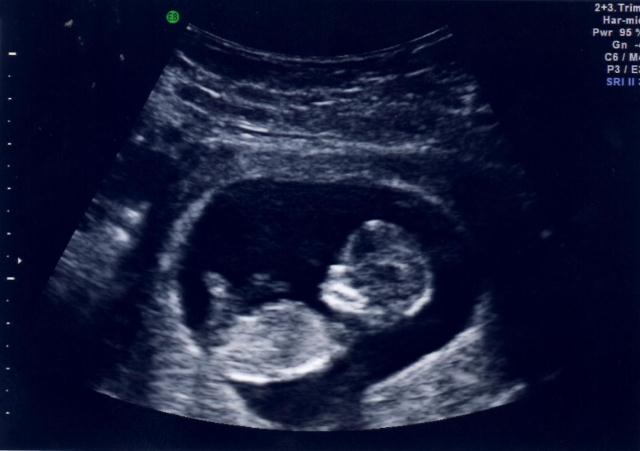

I just joined the forum. This is our first baby and I'm anxious to know the gender :)

I have been reading lately about the nub and skull theory. I think I can see a faint nub in my pic.

Any guesses on gender?

Am I crazy that I can see a faint nub in the 1st picture? I'm no expert, so help me out if you've been doing this for awhile.

Any other guesses? Can anyone see the nub in the first pic?